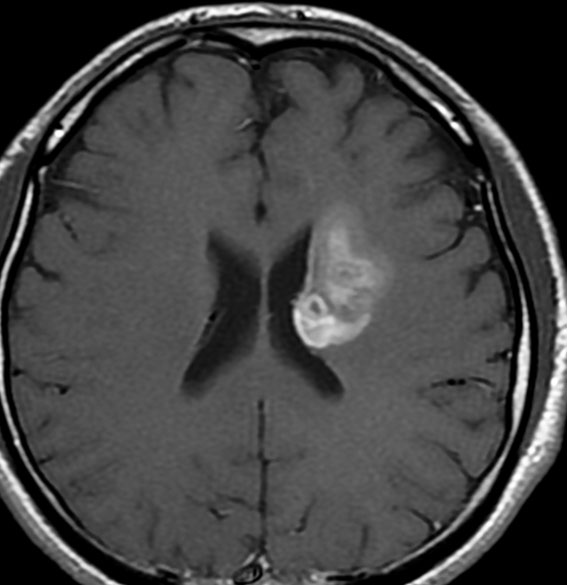

典型的なスード・プログレッション

放射線治療前

若い男性です。ある病院で生検術が行われたのですが病理診断がはっきりしませんでした。強度変調放射線治療 IMRT 54グレイ・27分割の放射線治療を行いました。左大脳基底核の乏突起膠腫系腫瘍と考えられたので,増強病変外マージンは10mmととても狭い領域で46グレイ・23分割と低い線量に押さえられています。テモダール 75mg/m2を放射線治療期間中に併用しています。左はガドリニウム増強MRI,右はFLIAR(フレア) 画像。